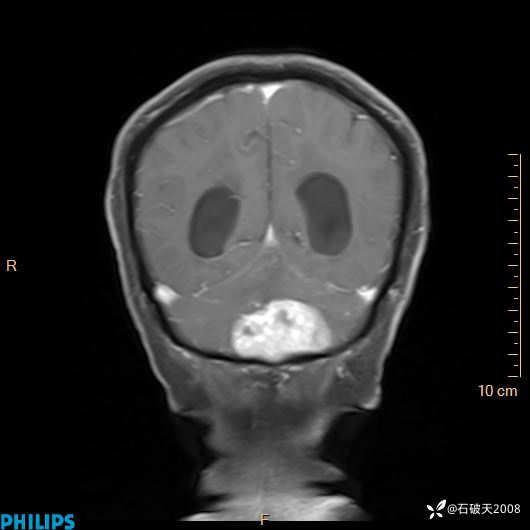

书上说这个肿瘤发生在幕下仅4.09%,你会想到它吗?(病理已公布)

女 86岁 主 诉:乏力1月

现病史:患者1月前活动出现双下肢乏力,无头晕、头痛、恶心、呕吐、肢体活动不利,休息后缓解,间断断发作,症状进行性加重,在家口服药物治疗(具体不详),效差,为进一步诊治,来我院,门诊按“乏力”收住我科,患者自发病以来,神志清,精神稍差,饮食睡眠欠佳,大小便正常,体重未见明显改变。

增强冠状位